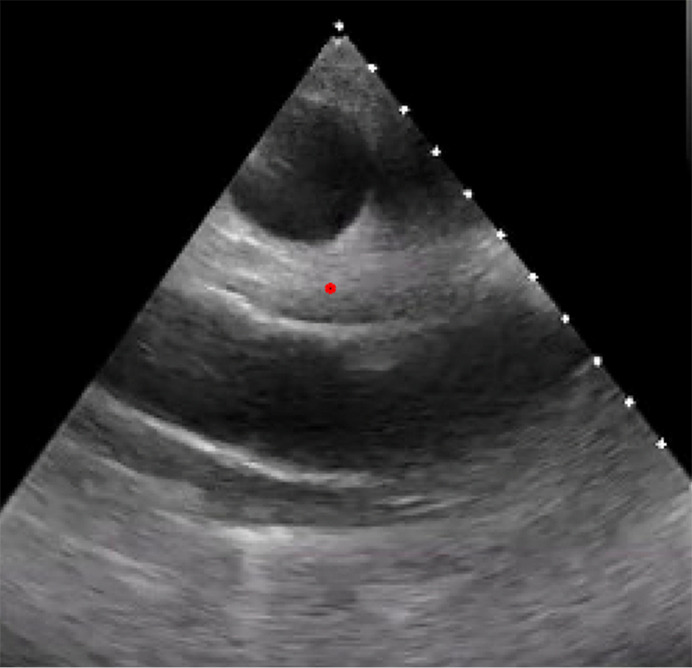

背景和目的:最近主要的国际社会指南强调了多模态成像在感染性心内膜炎(IE)评估中的应用。本文旨在通过实际案例讨论多模态成像在IE中的当代应用,展示如何使用新兴的成像方式,包括心脏计算机断层扫描(CCT)和核成像技术。方法:检索PubMed数据库2024年01月01日至2024年10月01日的文献。我们的综述使用了有关“感染性心内膜炎”和“多模态成像”的相关文章。从克利夫兰诊所基金会的四个临床病例被纳入补充这一文献综述与现实世界的例子。主要内容和发现:本文献综述包括国际心脏病学指南、调查研究、荟萃分析和专门的综述,重点介绍了不同成像方式在IE评估中的具体作用、优势和劣势,包括经胸和经食管超声心动图(TEE)、CCT、18f -氟脱氧葡萄糖正电子发射断层扫描(18F-FDG PET)和白细胞单光子发射计算机断层扫描(WBC SPECT)。这篇综述表明,鉴于越来越复杂的患者群体和越来越多的假体瓣膜和装置,这些多模态成像工具的新兴作用。结论:本文结合复杂的临床病例,讨论了目前的文献和指南,目的是说明多模态心脏成像在IE中的相对优势和劣势,以及适当的应用。

Background and objective: Recent major international society guidelines have highlighted the utility of multi-modality imaging in the evaluation of infective endocarditis (IE). This article aims to discuss the contemporary applications of multimodality imaging in IE through real-life cases, demonstrating how emerging imaging modalities, including cardiac computed tomography (CCT) and nuclear imaging techniques can be used.

Key content and findings: This literature review encompasses international cardiology guidelines, as well as investigational studies, meta-analyses, and dedicated reviews highlighting the specific roles, strengths, and weaknesses of different imaging modalities in the evaluation of IE, including transthoracic and transesophageal echocardiography (TEE), CCT, 18F-fluorodeoxyglucose positron emission tomography (18F-FDG PET), and white blood cell single-photon emission computed tomography (WBC SPECT). This review demonstrates the emerging role for these multi-modality imaging tools in light of an increasingly complex patient population with growing numbers of prosthetic valves and devices.